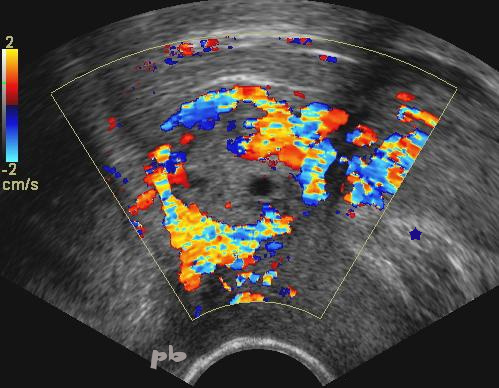

36- GEU interstitielle

(même patiente que 35)

- Agrandissement permettant de mieux distinguer l’embryon (★). Pas d’activité cardiaque.

- Vascularisation périphérique.

- Contours utérins (►).

36 – Interstitial pregnancy (same patient as 35)

Enlargement allowing better distinction of the embryo (★ ). No cardiac activity.

Peripheral vascularization.

Uterine contours ( ►).